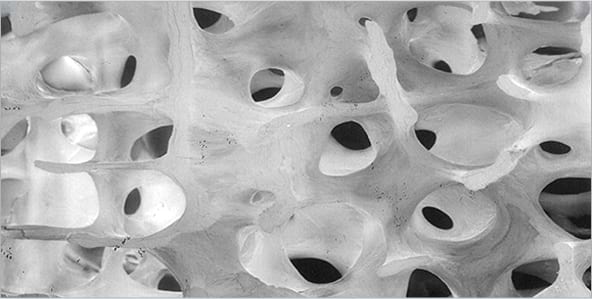

隨著年齡的增長,身體內的荷爾蒙轉變會令骨骼礦物質漸漸流失。骨質流失的第一階段稱為骨質密度偏低,即表示你的骨骼逐漸變得薄弱。骨骼的分降速度比形成的速度快,而骨骼的強度和結構亦會隨時間變得差。2,3

健康骨骼

正常骨質密度

骨質疏鬆性骨骼

低骨質密度

- 骨骼是一種活細胞,構成身體的強健結構,可支撐及保護身體。人體會不斷重建新骨骼並取代舊骨骼。 3

- 如你患有骨質疏鬆症,骨骼的分解速度會較重建的速度快,以致骨骼變得脆弱。因此,即使只是輕微的碰撞或跌倒都會容易發生骨折。5,6

以上圖像已獲David Dempster授權重新製作和使用。